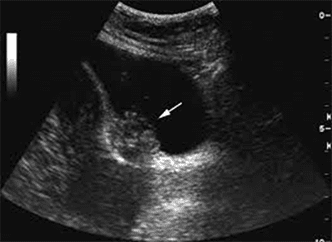

Op een echo zijn ook organen in het kleine bekken te zien. Dit zijn de vagina, baarmoeder, eileiders en de eierstokken. Maar ook de blaas en de endeldarm. Omdat onze gynaecologen bekend zijn met endometriose herkennen ze de kenmerken op de echo. De uitslag van het echografisch onderzoek is direct beschikbaar. De gynaecoloog kan dus aan het eind van je afspraak aangeven of je of endometriose hebt en in welke mate. Blijkt na je eerste afspraak dat er aanvullend onderzoek nodig is dan wordt een MRI-scan gemaakt.

Expertise echo endometriose in de blaaswand